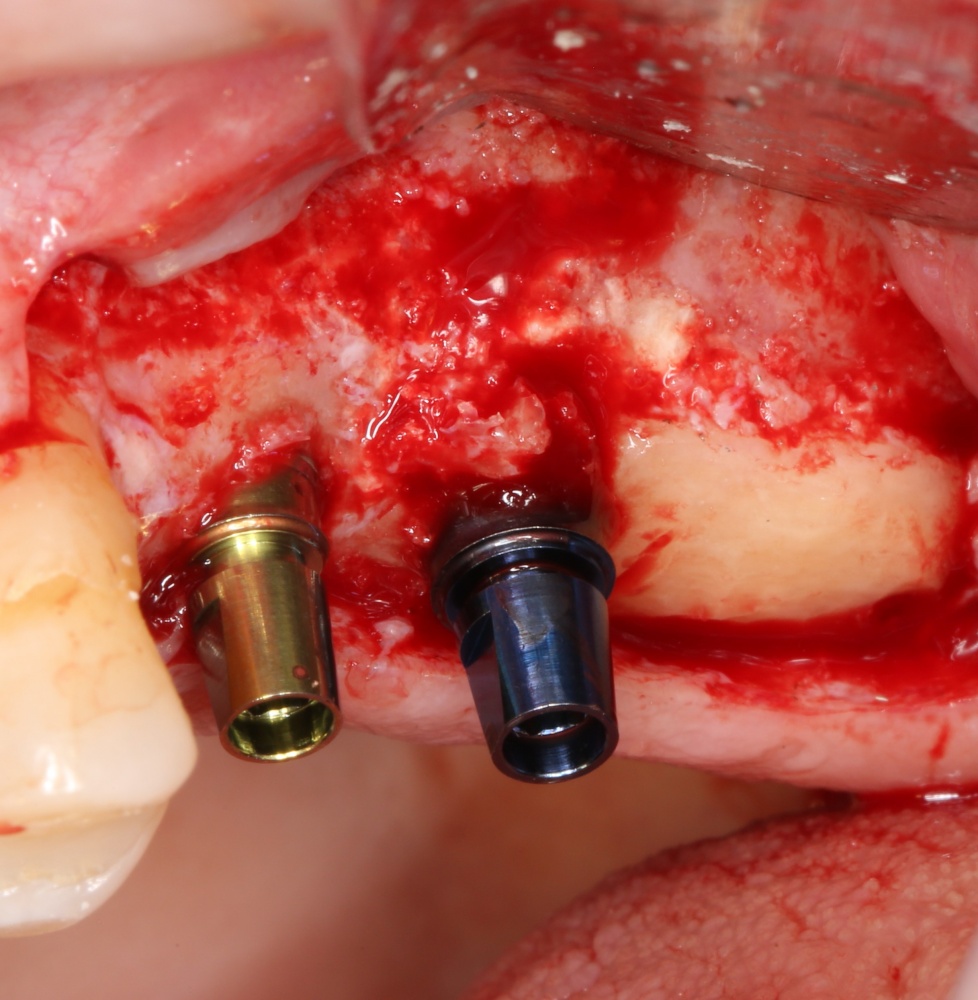

Кстати, обрати внимание на ширину альвеолярного гребня (левая картинка). Она чуть меньше 3 мм. Это объясняет, почему я засомневался в возможности установки имплантатов одновременно с остеопластикой. Понятно и без КЛКТ.

Возвращаемся к основной операционной области. Еще раз посмотрим на альвеолярный гребень, поофигеваем от его ширины и моих грандиозных планов:

Я зафиксировал костный блок практически без адаптации на несколько винтов. Обрати внимание, что винты находятся в зоне, где не планируется установка имплантатов. Фиксация должна быть надежной, поскольку мне еще предстояла подготовка лунок для имплантатов. Трех винтов для этого вполне достаточно.

Напомню, что для этой работы я выбрал субкрестальные имплантаты Ankylos C/X. Они прекрасно сочетаются с любым методом остеопластики.

Глянем на то, что получилось: